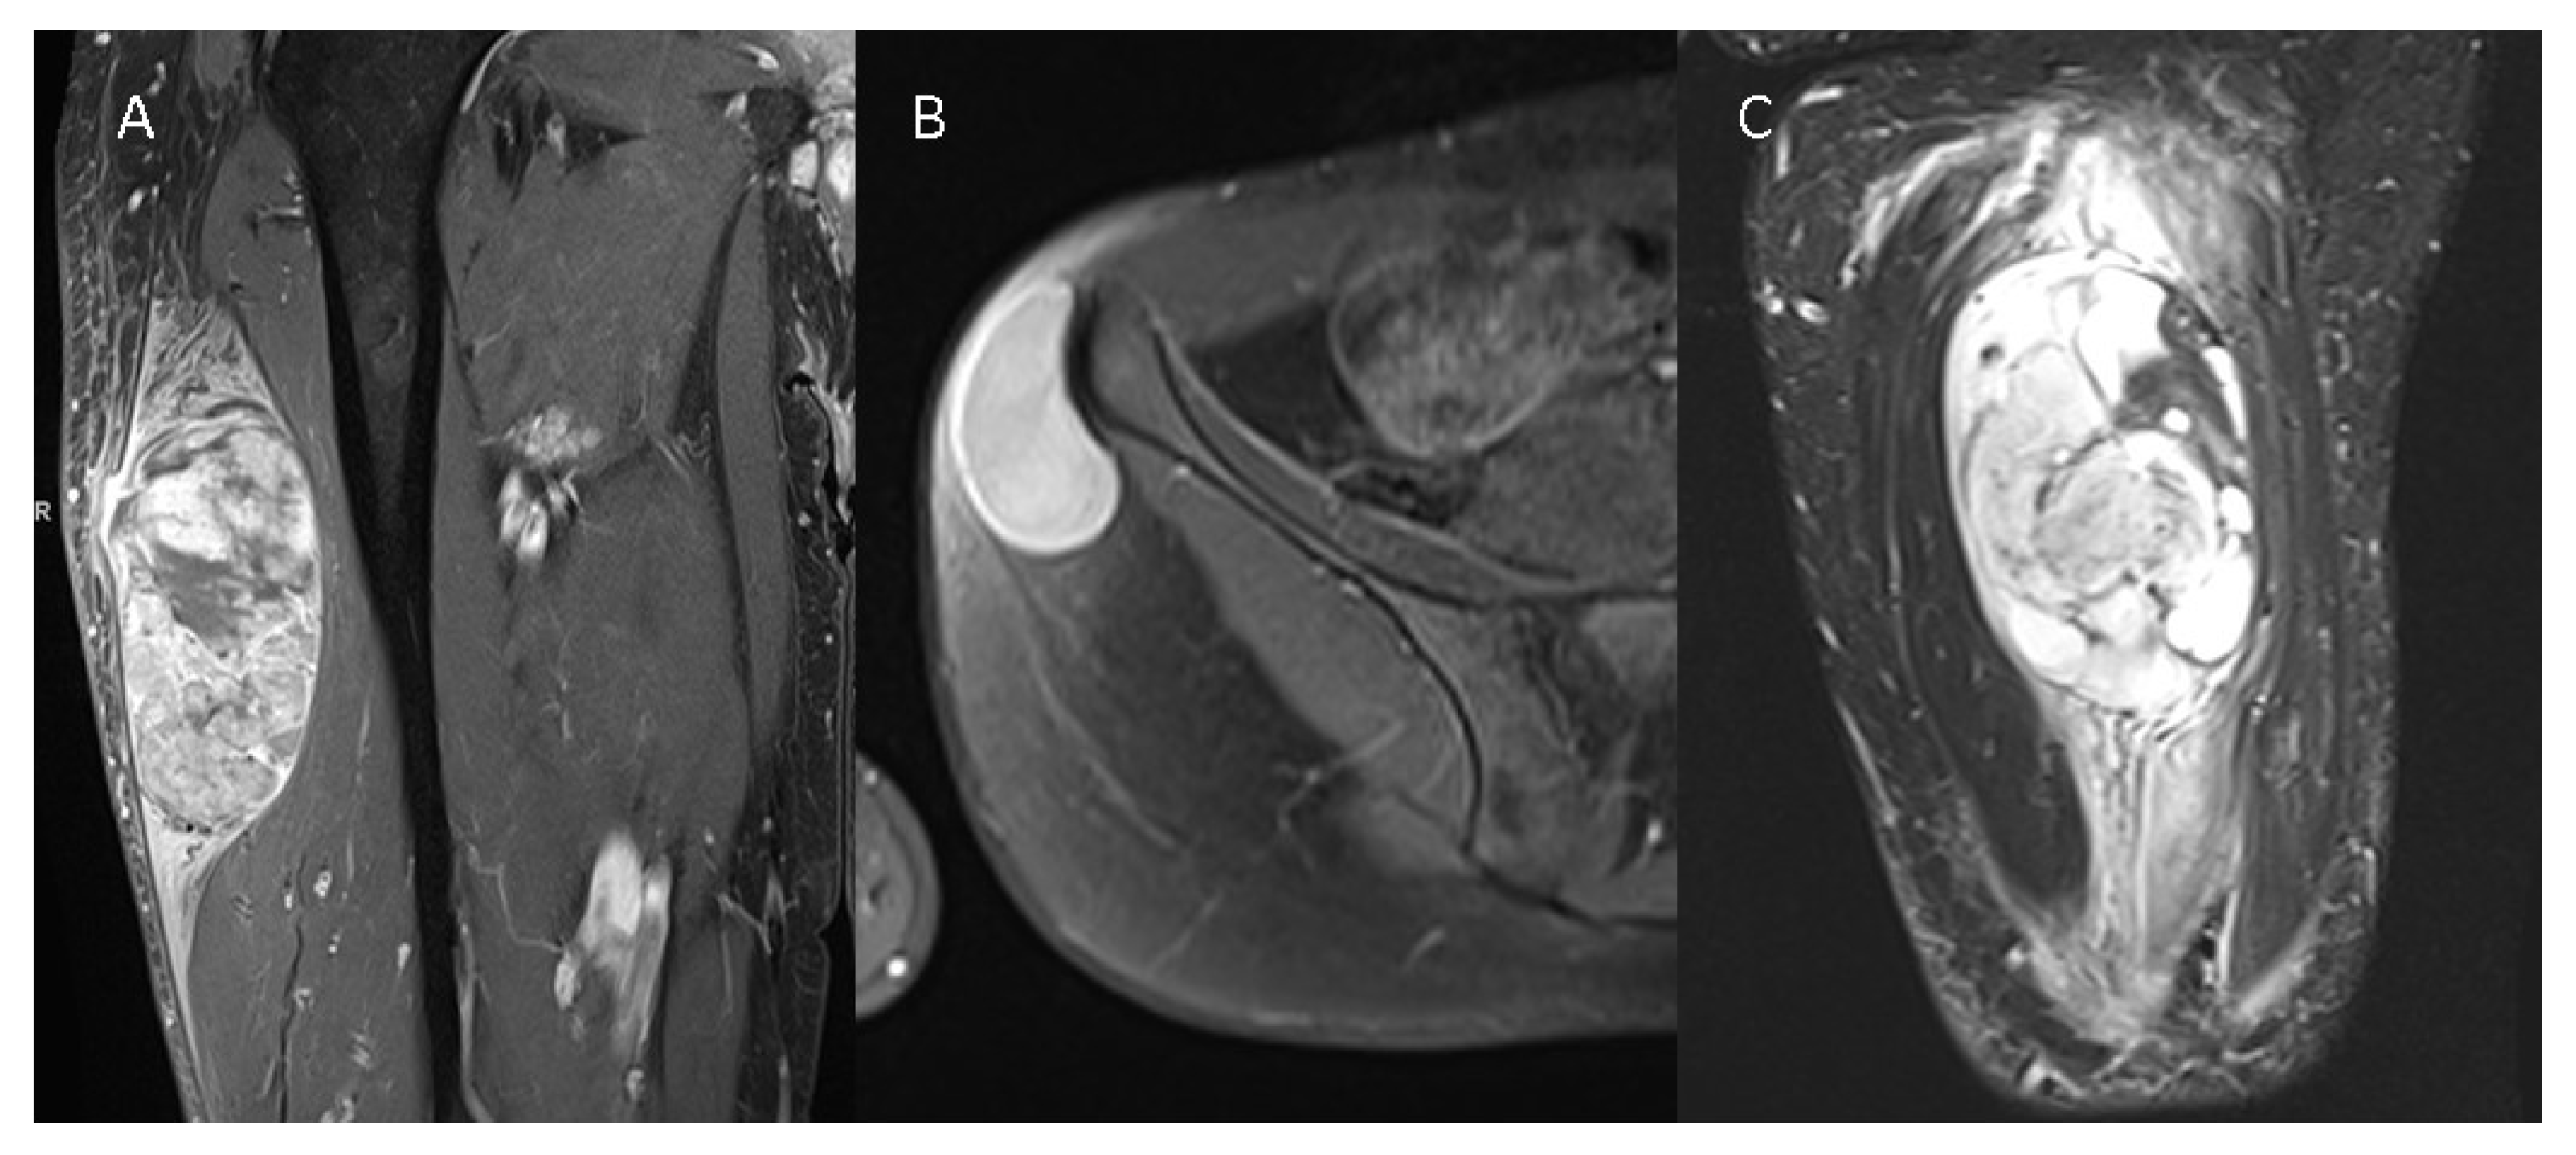

High-grade tumors were significantly larger, with a mean tumor volume of 99.11 mL (±68.82 mL) in low-grade tumors compared to 127.83 mL (±65.73 mL) in high-grade tumors. While the ovoid form was the most frequently observed configuration in G1 tumors (64% of all G1 tumors), the multilobulated/polycyclic configuration was predominant in high-grade tumors, reported in approximately 73% of all high-grade cases. Tumor heterogeneity significantly varied between low-grade and high-grade STSs in T1w, T2w, and CE-T1w images (Table 2). Mean ADC values of the tumors within the ROIs were significantly higher in G1 tumors compared to G2/G3 tumors (1715 vs. 1250, p = 0.001). Likewise, the ratio of tumor mean ADC to healthy muscle mean ADC exhibited a significant difference (p = 0.005) between low-grade and high-grade STSs. Tumor margins were significantly more often less defined in high-grade tumors (T1w: p = 0.005, T2w: p = 0.002, CE-T1w: p = 0.009). No significant difference was observed in the extent of intratumoral hemorrhage (p = 0.247), cystic degeneration (p = 0.107), or macroscopic necrosis (p = 0.108, Table 2). In total, 86% of all high-grade tumors displayed intense intratumoral contrast enhancement, while 76% of the low-grade tumors did (p = 0.169). Peritumoral edema was significantly more severe in high-grade tumors, with 16.5% exhibiting mild peritumoral edema, 37% showing moderate peritumoral edema, and 32.99% displaying severe peritumoral edema. In contrast, 75% of all low-grade tumors demonstrated no peritumoral edema (p < 0.001). Similar results were observed for peritumoral contrast enhancement, with 71% of all G1 tumors displaying no peritumoral enhancement, while only 13% of all G2/G3 tumors showed no peritumoral contrast enhancement (p < 0.001). Figure 1 presents three different STSs.

Figure 1.

Three different STSs are illustrated—(A) G3 pleomorphic liposarcoma with peritumoral contrast enhancement and intratumoral heterogeneity on a contrast-enhanced T1w image, (B) G1 spindle cell sarcoma without peritumoral contrast enhancement and homogenous intratumoral enhancement on a contrast--enhanced T1w image, and (C) G2 myxofibrosarcoma of the thigh with extensive peritumoral edema on a T2 TIRM image.